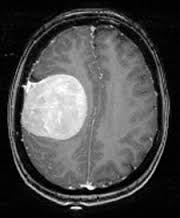

APP demo - https://www.youtube.com/watch?v=xbZUBd_1fSQ Presentation - https://www.youtube.com/watch?v=trTC5IrCSWA A doctor/ patient can make an account on our web app and then he can go to the "scans" page and upload an x-ray/ MRI of a specific organ. Our AI algorithms will detect if a disease is present in that scan.

This is a dynamic web app that uses artificial intelligence so this makes it a very complex the app when it comes to the backend part. We used the python programming language as it is very easy to program with it and is probably the best programming language for data science. Python also has some very good web engines. We used the Jinja template engine used by Flask in python. Flask is a very good choice in this case as it is highly customizable has many useful libraries and is very well documented. For the forms, we used - Flask-WTF For the login dynamic - Flask-login For the database, we use a Postgres link connection with Flask-SQLaclhemy We also need a background worker for Artificial Intelligence algorithms as they take a long time and making the user wait is not an option in this case, especially if they have a slow internet connection. As a python client, we used Redis and RQ workers to send background jobs in the queue. For the artificial intelligence algorithms, we used, ( along with popular linear algebra libraries like NumPy ), the TensorFlow library which is the most popular neural network library and it provides powerful algorithms like ResNet50, which we used to train the Brain Tumor and Pneumonia algorithms. The datasets come from Kaggle. Brain tumor dataset: https://www.kaggle.com/navoneel/brain-mri-images-for-brain-tumor-detection Pneumonia dataset: https://www.kaggle.com/c/rsna-pneumonia-detection-challenge We had to show the results in a web page and we did that by making a waiting web page that refreshes every 10 seconds and therefore sends a request every 10 seconds, in that request, we also check if the background job is ready. If it is ready to take the output, ( the image ha to be converted to bytes encoded in utf-8 as this is the safe and sure way of transferring images through workers). We hosted our app with Heroku ( paid for hobby plan so the app won’t sleep) as it is very easy to use workers, postgress, make multiple uploads, etc.